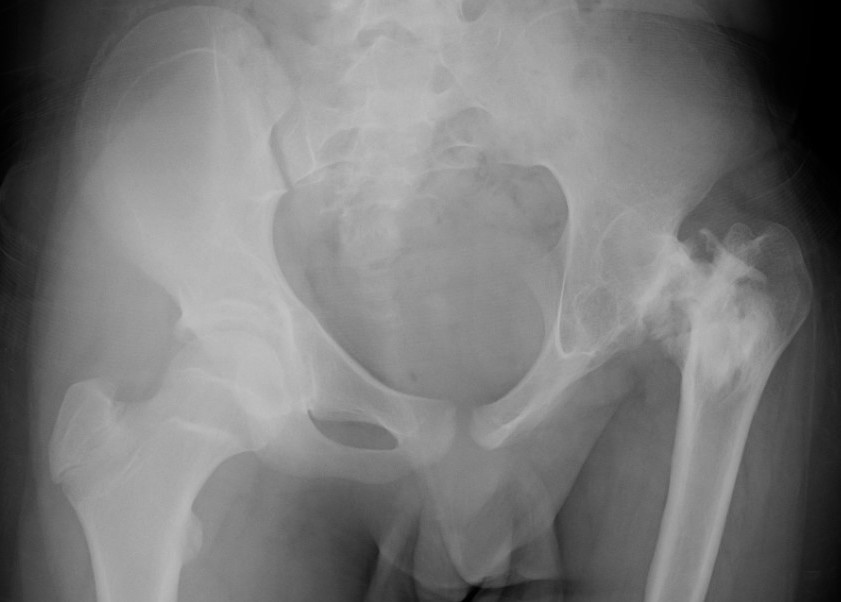

Xray

Normal with transient synovitis

Hip subluxation with septic arthritis

Septic arthritis

SCFE / Perthes